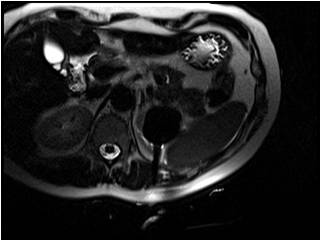

MRI-guided renal cryoablations.

The Tumor Ablation Program has performed over 400 MRI-guided renal cryoablations.